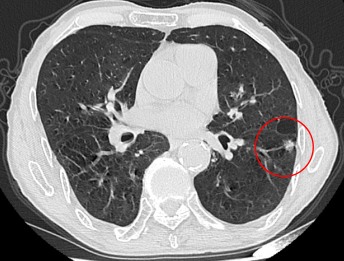

近日,重庆医科大学附属璧山医院(重庆市璧山区人民医院)呼吸介入团队成功为一名九旬高龄患者进行了高危肺结节微波消融术,术后恢复良好。